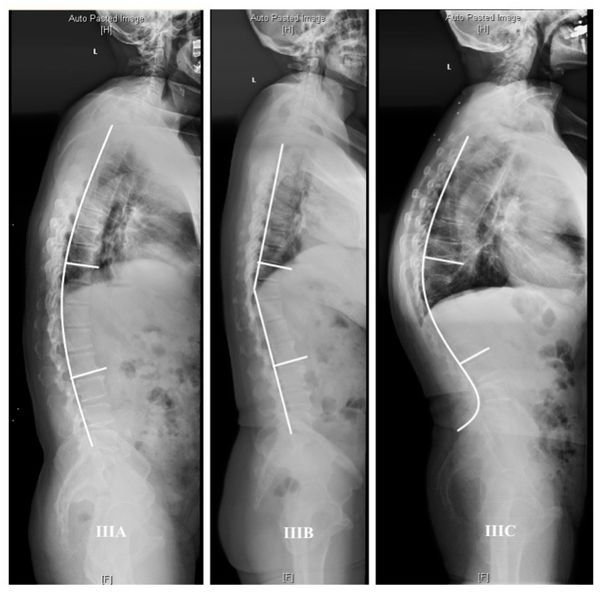

В классификации ASD–SRS–Schwab выделяют фронтальную и сагиттальную деформацию. Чтобы оценить степень этой деформации, нужно сопоставить её выраженность со степенью болевого синдрома и ограничением физической активности [14]. В классификации учтены деформации более 30°.

В зависимости от локализации угла сколиоза выделены следующие типы фронтальной дуги:

Диагностическую ценность при нарушении осанки имеет рентгенографическое исследование с функциональными пробами. Рентгенография помогает определить, в каком отделе позвоночника есть деформация и насколько она выражена. Также на рентгенограмме видно ротацию позвонков (поворот вокруг своей оси), их смещение вбок, вперёд или назад и степень смещения [17]. Боковая проекция позволяет определить грудной и крестцовый кифоз, шейный и поясничный лордоз, а также оценить сагиттальный баланс позвоночника.